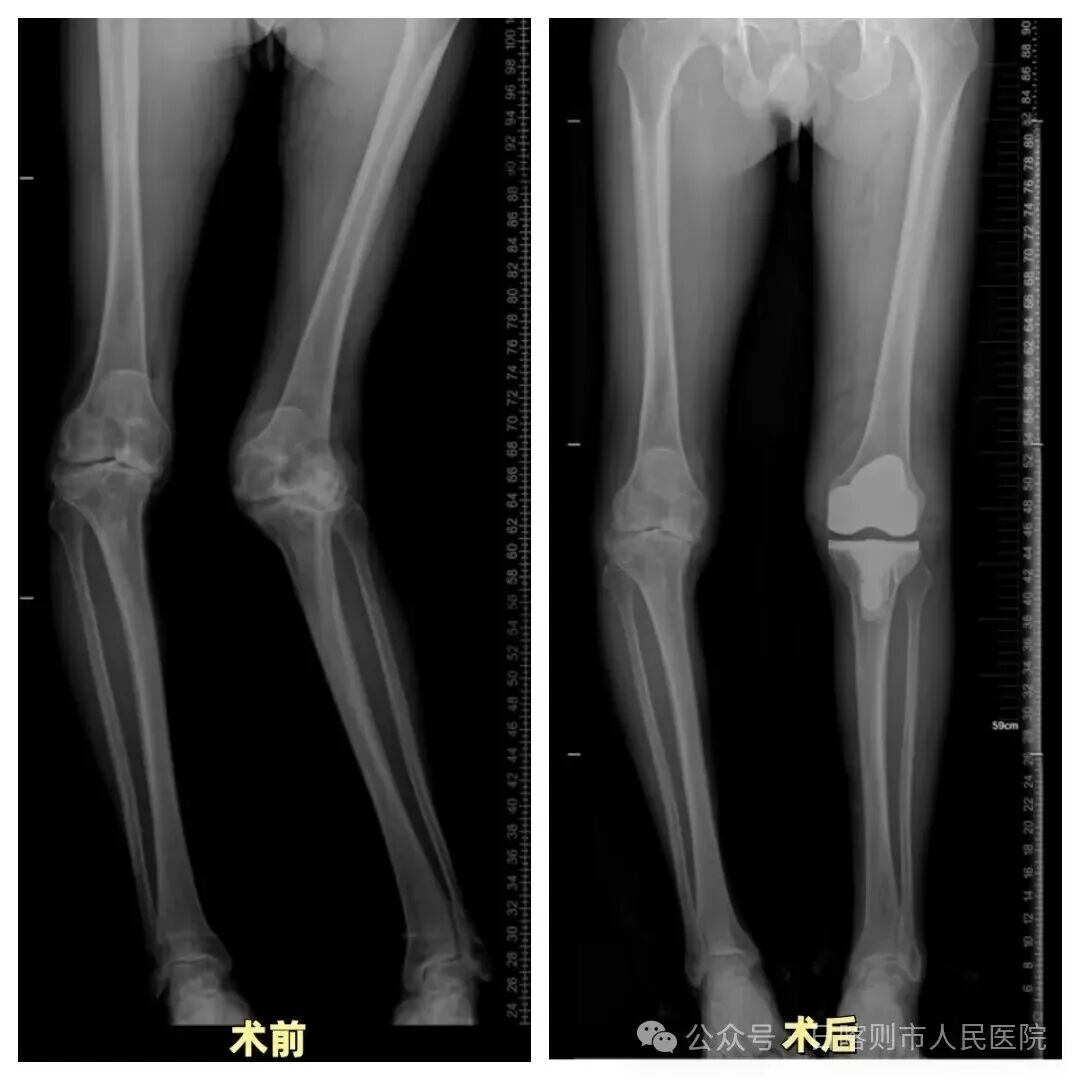

▲典型病例1:60余岁男性,双侧膝骨关节炎,左膝外翻合并胫骨近端骨缺损